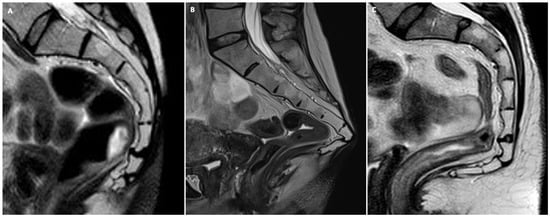

- Anal sphincter complex: This shows variable composition and signal intensity on axial T2-weighted images depending on the level. The upper part consists of the internal sphincter, longitudinal muscle, and puborectal muscle. The middle part features the intersphincteric space, which appears as a high-signal-intensity, slit-like space between the internal sphincter (5 mm thick, intermediate signal intensity) and the external sphincter (1.5 mm thick, low signal intensity). A thin hypointense circular structure within this space represents the longitudinal muscle, which is a continuation of the outer longitudinal smooth muscle of the rectum. The lower part contains the external sphincter and the longitudinal muscle layer. On mid-coronal T2-weighted images, the thicker inner layer is formed by the two halves of the internal sphincter in apposition, while the intersphincteric space is visible as a thin, high-signal-intensity layer. At the outer margin, a cleft divides the puborectalis muscle (above) from the external sphincter (below). On midsagittal T2-weighted MR images, the anal sphincter appears as a low-signal-intensity, homogeneous, cylindrical structure, approximately 4 cm long, composed of muscle layers extending from the attachment of the levator ani muscle to the rectum. Lastly, the perianal spaces are clearly seen as two symmetrical, high-signal-intensity, fat-containing, pyramid-shaped spaces surrounding the hypointense anal canal, with multiple fibrous septa. The apex is visible at the origin of the V-shaped levator ani muscle, along with the supralevator space above it.